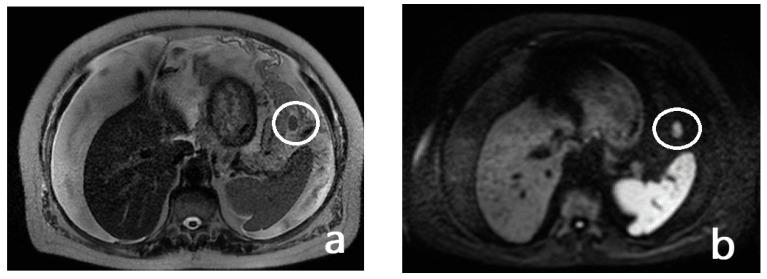

Peritoneal carcinosis is a condition characterized by the spread of cancer cells to the peritoneum, which is the thin membrane that lines the abdominal cavity. It is a serious condition that can result from many different types of cancer, including ovarian, colon, stomach, pancreatic, and appendix cancer. The diagnosis and quantification of lesions in peritoneal carcinosis are critical in the management of patients with the condition, and imaging plays a central role in this process. Radiologists play a vital role in the multidisciplinary management of patients with peritoneal carcinosis. They need to have a thorough understanding of the pathophysiology of the condition, the underlying neoplasms, and the typical imaging findings. In addition, they need to be aware of the differential diagnoses and the advantages and disadvantages of the various imaging methods available. Imaging plays a central role in the diagnosis and quantification of lesions, and radiologists play a critical role in this process. Ultrasound, computed tomography, magnetic resonance, and PET/CT scans are used to diagnose peritoneal carcinosis. Each imaging procedure has advantages and disadvantages, and particular imaging techniques are recommended based on patient conditions. Our aim is to provide knowledge to radiologists regarding appropriate techniques, imaging findings, differential diagnoses, and treatment options. With the advent of AI in oncology, the future of precision medicine appears promising, and the interconnection between structured reporting and AI is likely to improve diagnostic accuracy and treatment outcomes for patients with peritoneal carcinosis.

腹膜癌是一种以癌细胞扩散至腹膜为特征的病症,腹膜是衬于腹腔的一层薄膜。它是一种严重的病症,可由多种不同类型的癌症引发,包括卵巢癌、结肠癌、胃癌、胰腺癌和阑尾癌。腹膜癌中病变的诊断和定量对于该病症患者的管理至关重要,而影像学在这一过程中发挥着核心作用。放射科医生在腹膜癌患者的多学科管理中起着至关重要的作用。他们需要对该病症的病理生理学、潜在肿瘤以及典型的影像学表现有透彻的了解。此外,他们需要知晓鉴别诊断以及各种可用影像学方法的优缺点。影像学在病变的诊断和定量中起着核心作用,放射科医生在这一过程中起着关键作用。超声、计算机断层扫描、磁共振成像和正电子发射断层显像/计算机断层扫描(PET/CT)用于诊断腹膜癌。每种成像检查都有其优缺点,会根据患者情况推荐特定的成像技术。我们的目的是向放射科医生提供有关合适技术、影像学表现、鉴别诊断和治疗方案的知识。随着人工智能在肿瘤学中的出现,精准医学的未来似乎很有前景,结构化报告与人工智能之间的相互联系可能会提高腹膜癌患者的诊断准确性和治疗效果。